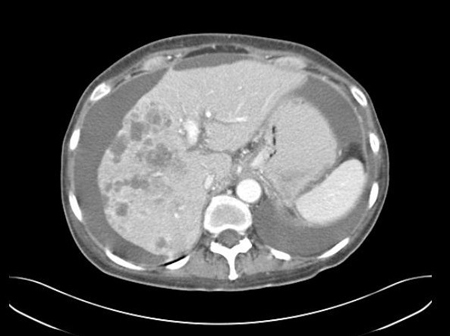

CT abdomen with intravenous contrast, revealing numerous enhancing lesions in the right hepatic lobe, with associated ascites. Percutaneous biopsy of one of these hepatic lesions revealed adenocarcinoma, but no primary site was identified during routine workup. This is a typical presentation of ACUP

From the personal collection of Dr D. Cosgrove